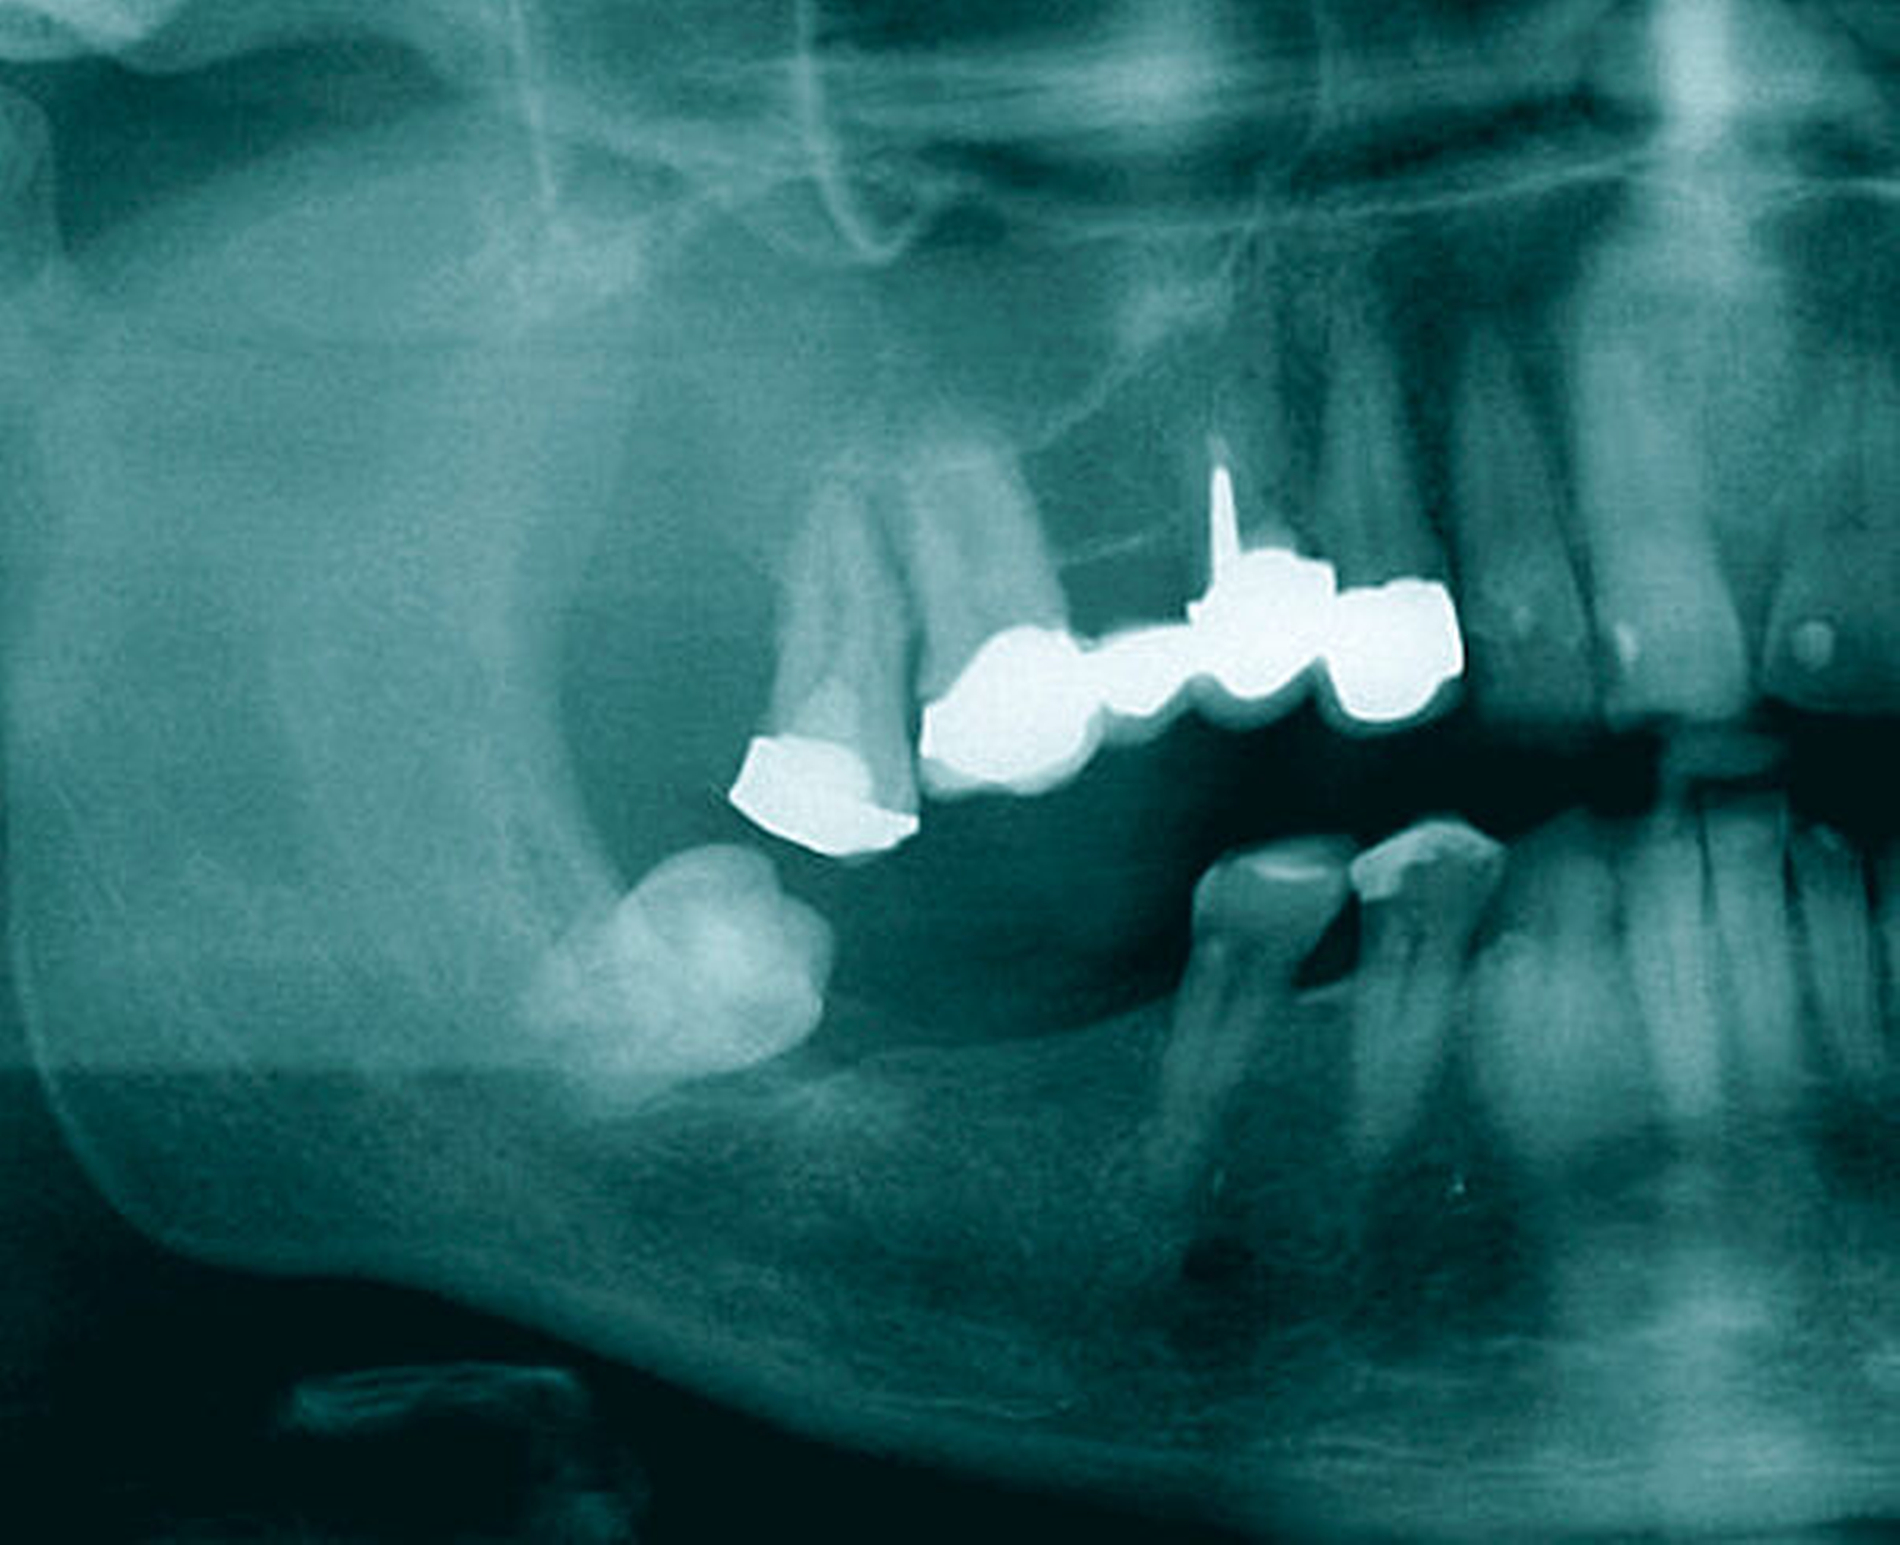

Ein 50-jähriger Patient ohne Nebenerkrankungen und Medikation stellte sich auf Überweisung seines Hauszahnarztes mit einem unklaren, tumorähnlichen Befund im rechten Oberkiefer vor. Intraoral zeigte sich vor allem distal des Zahns 17 eine fibrinbelegte, ulzerierend erscheinende Läsion. Die Zähne 17 und 16 reagierten negativ auf eine Vitalitätsprobe und wiesen einen Lockerungsgrad von I bis II auf. Insbesondere der Zahn 17 war mit seiner partiell freiliegenden Wurzeloberfläche auffällig (Abbildung 1). Eine Panoramaschichtaufnahme erbrachte den Nachweis einer starken Elongation des oberen, rechten zweiten Molaren mit erweiterten Parodontalspalt (Abbildung 2).